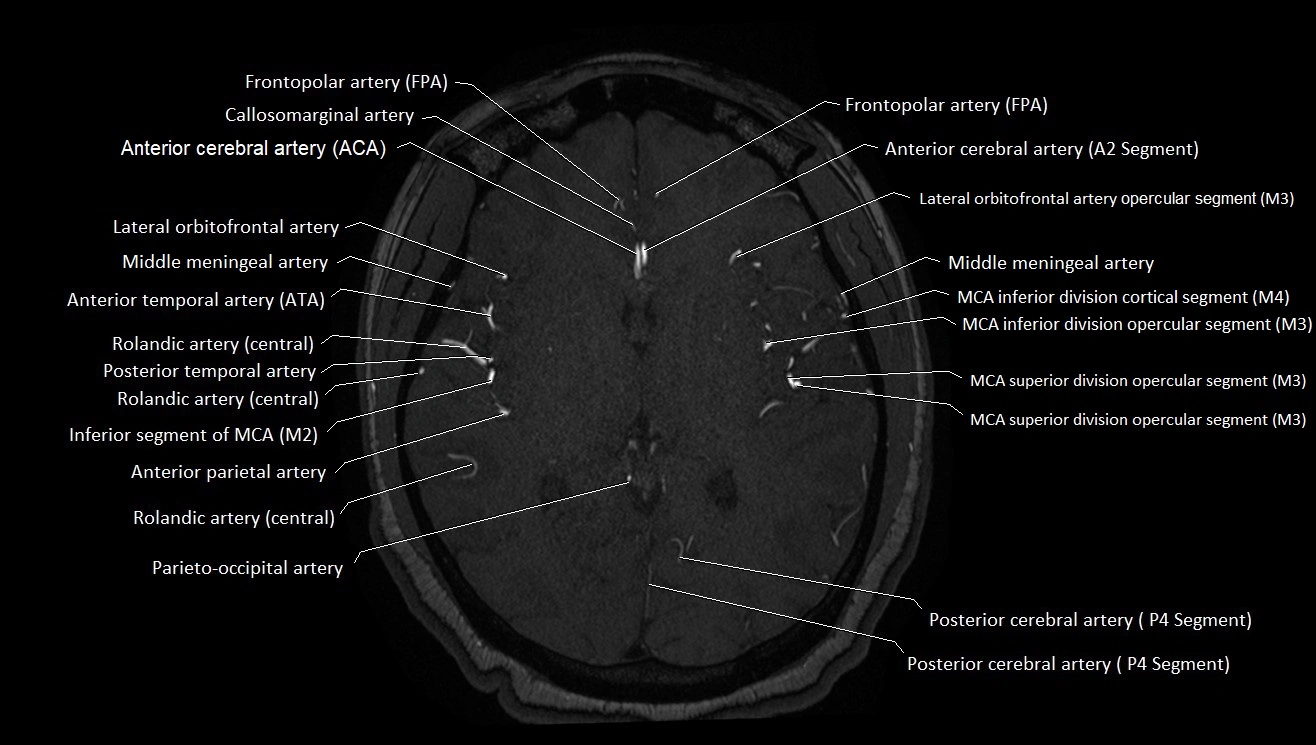

MRA (Magnetic Resonance Angiography):

• Flow-related enhancement makes the AChA appear as a bright, linear vascular signal against suppressed background

• High sensitivity for origin and proximal course; distal branches may be too small to resolve

• Detects stenosis, occlusion, aneurysm, AVM feeders

MRI images

image